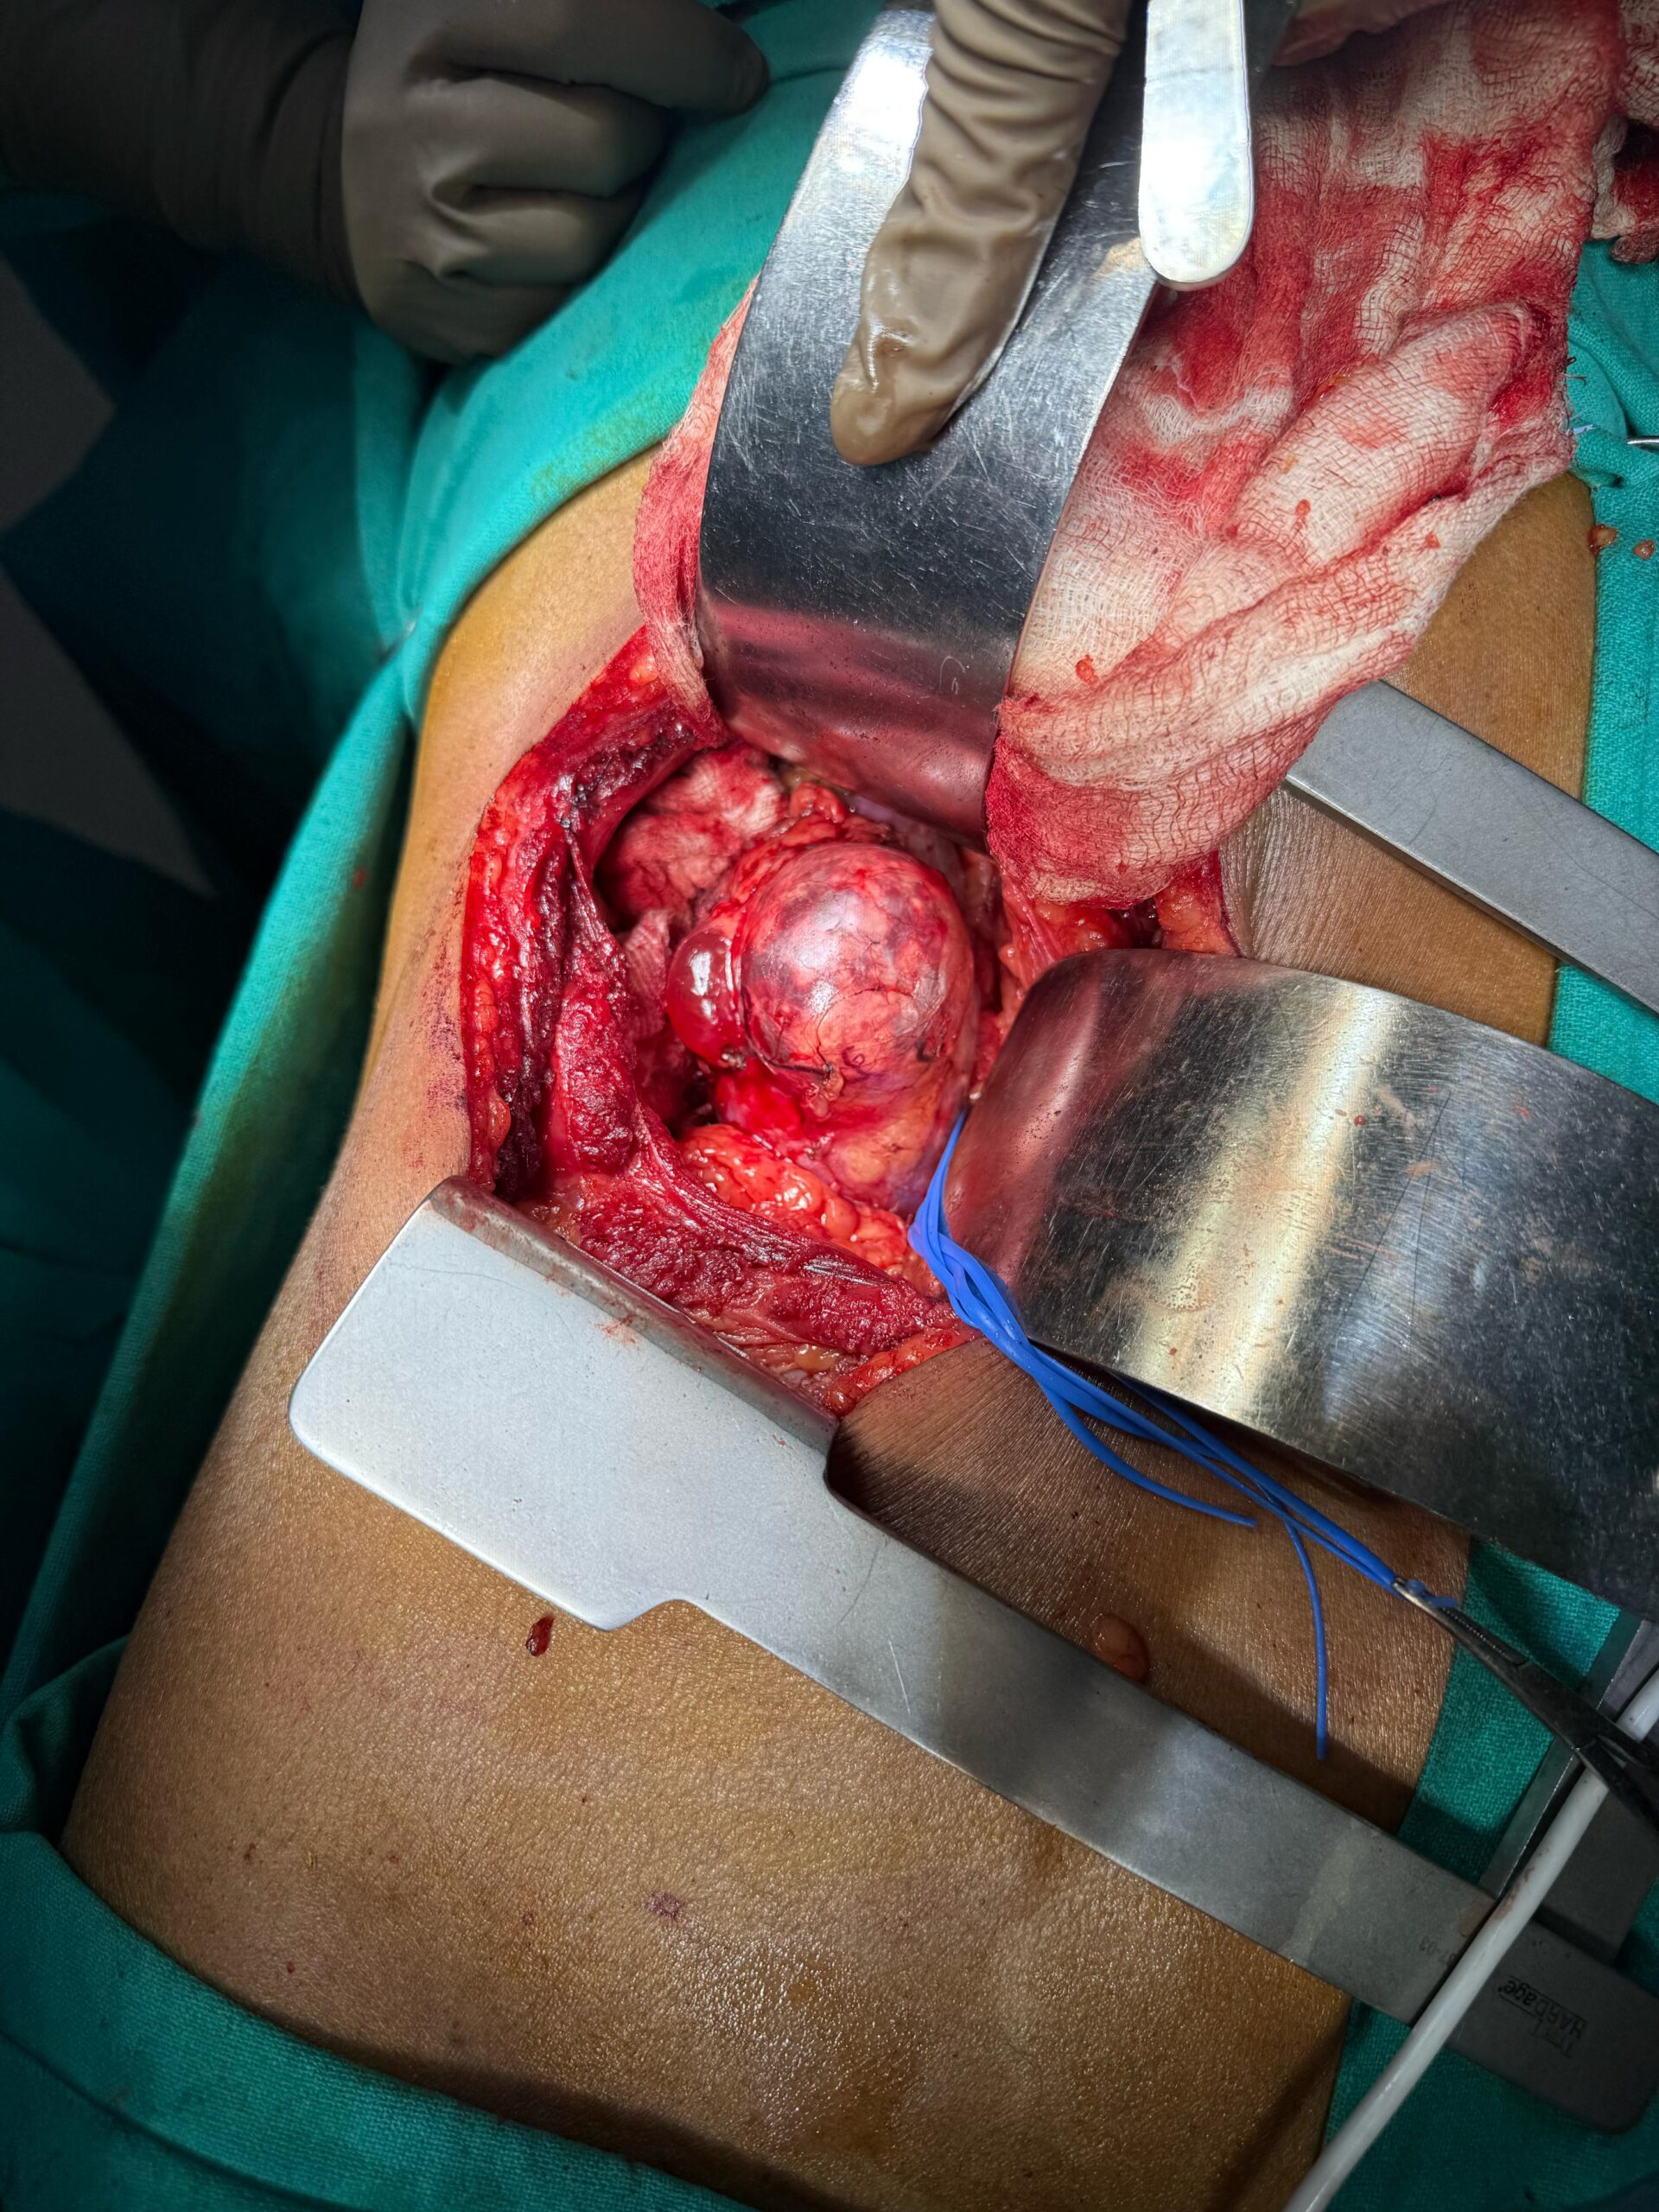

Our Gallery